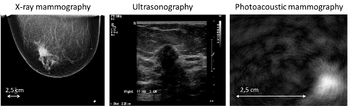

Optical mammography captures images without radiation, with greater patient comfort, and potentially fewer false positives, researchers say.

Researchers are in the first stages of testing a new technology that may allow radiologists to detect breast tumors with improved accuracy without exposing patients to radiation.